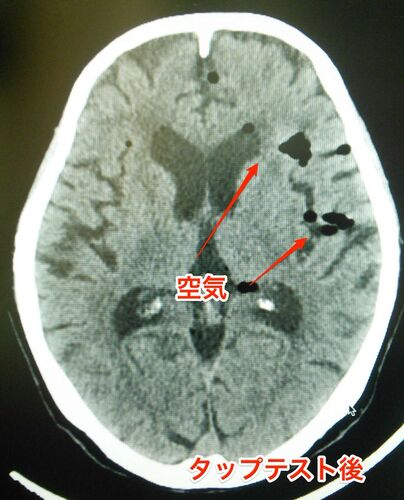

タップテスト(髄液排除試験)後に頭痛の訴えあり。何が起きたのか?

タップテスト(髄液排除試験)とは? タップテストとは、腰椎穿刺(腰椎の隙間から針を差し込む検査)を行い、脳脊髄液を採取する検査のことである。 髄膜炎や神経変性疾患が疑われる場合に行われるが、正常圧水頭症が疑われる場合には、脳脊髄液を抜いて症状が…